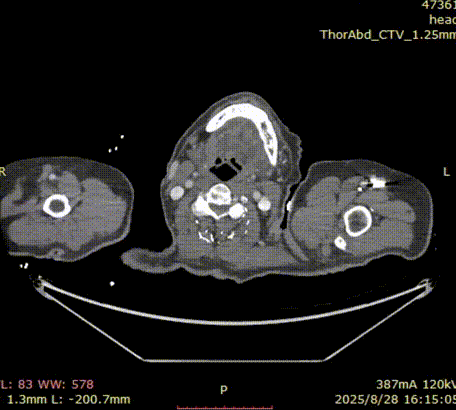

术前3D重建

gore医疗怎么样「胸有乾坤」千钧一发 转危为安——Gore TBE治疗急诊破裂TAA一例_https://www.jmylbn.com_新闻资讯_第11张

• 病人胸主动脉瘤破裂,病变累及LCCA;近端直径34-37mm。

• 弓上分支距离较近,INA与LCCA几乎无距离